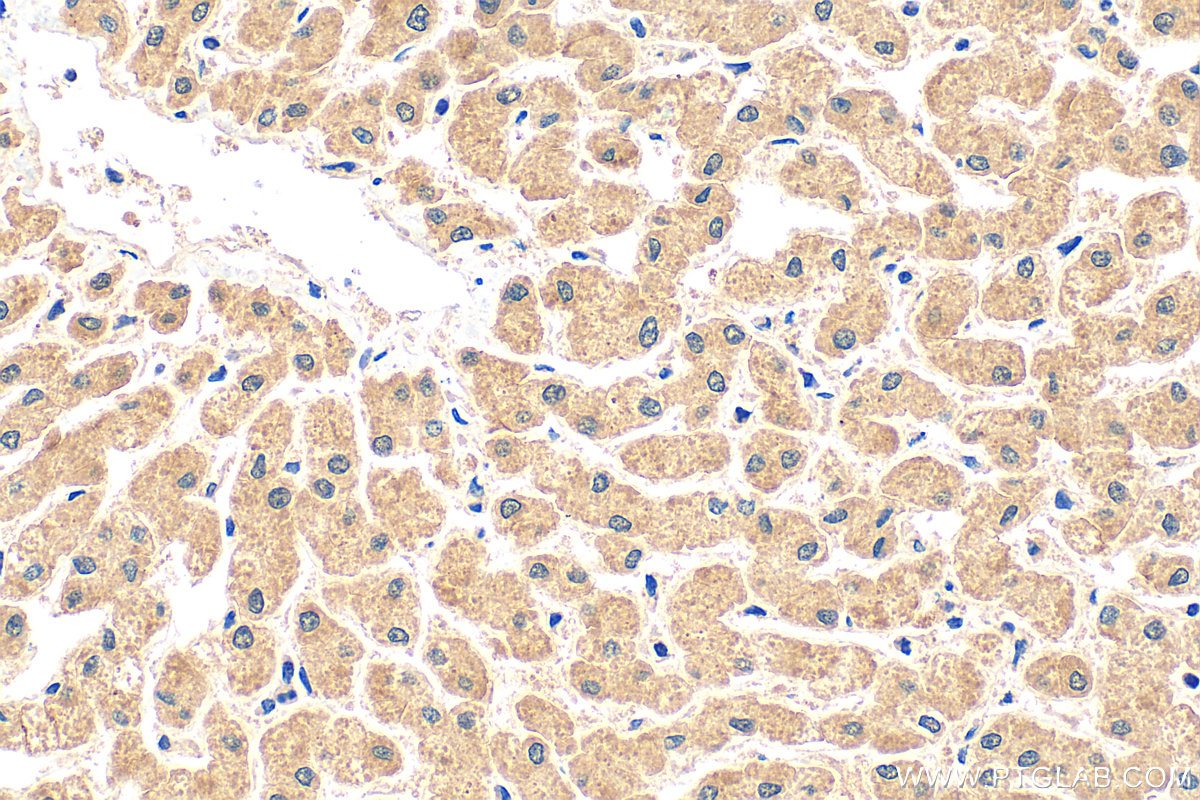

| Positive IHC detected in | human liver tissue Note: suggested antigen retrieval with TE buffer pH 9.0; (*) Alternatively, antigen retrieval may be performed with citrate buffer pH 6.0 |

17139-1-AP targets FBXL13 in IHC, ELISA applications and shows reactivity with human samples.